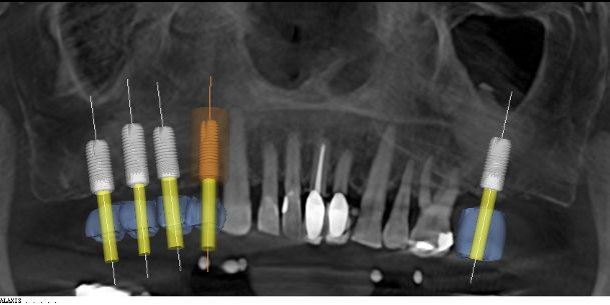

Using 3D X-Rays and a combination of regular and 3D impressions we get a perfect picture of your bone, teeth and jaw. The software “stitches” the X-Ray to the models and creates a full digital representation of the jaw. Using this precision digital model, we can experiment with different implant sizes and designs and perfect the angles of your implants. We can even plan the type of restoration we will be making for you. After all, the end goal is a new tooth – not just an implant. This produces the highest quality results in the safest and most predictable manner possible.

From the digital models, a surgical guide is fabricated by Sicat which has holes that exactly match our desired implant placement. The guides are placed in position during surgery. Using a special set of drills, the guide enables us to make the exact placements we have already planned within microns. Below are examples of computer-generated drill guides. There are various types of printed guides used for different situations.